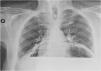

Se realizó radiografía de tórax (fig. 1) objetivándose la presencia de una cámara aérea ocupando ambos hemitórax, sugestivo de herniación gástrica o colónica. La tomografía computarizada (fig. 2) confirmó una hernia hiatal compleja tipo IV, que contiene la totalidad del estómago, duodeno, yeyuno, páncreas parcialmente y colon. El estómago se halló dilatado y rotado, sugestivo de vólvulo gástrico, aunque con adecuada captación parietal.